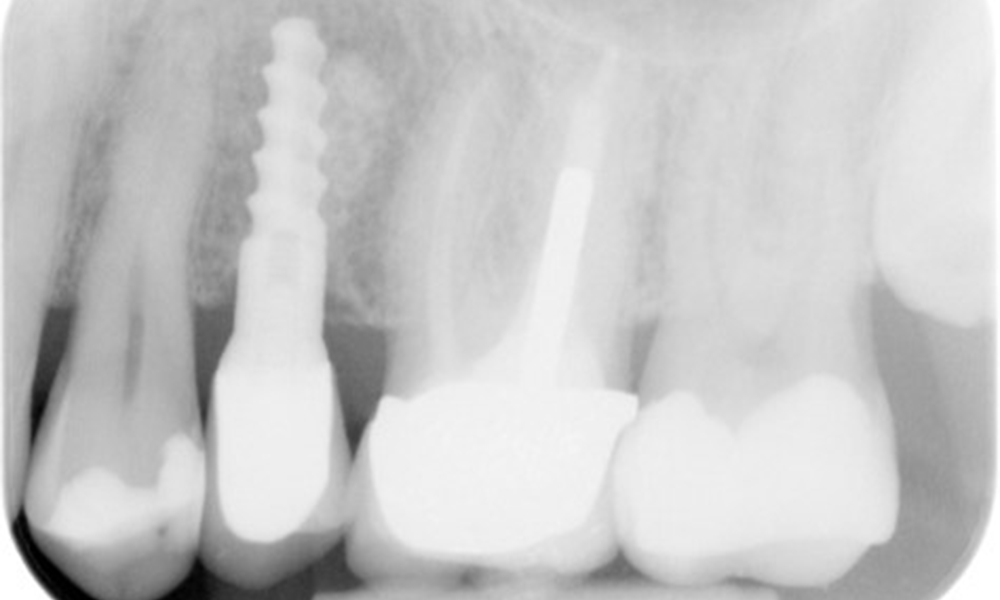

X-ray images (or bitewing X-rays)

X-ray images (or bitewing X-rays) taken on: 18/02/2021

The X-ray image shows the bone loss

The X-ray images show the bone loss.